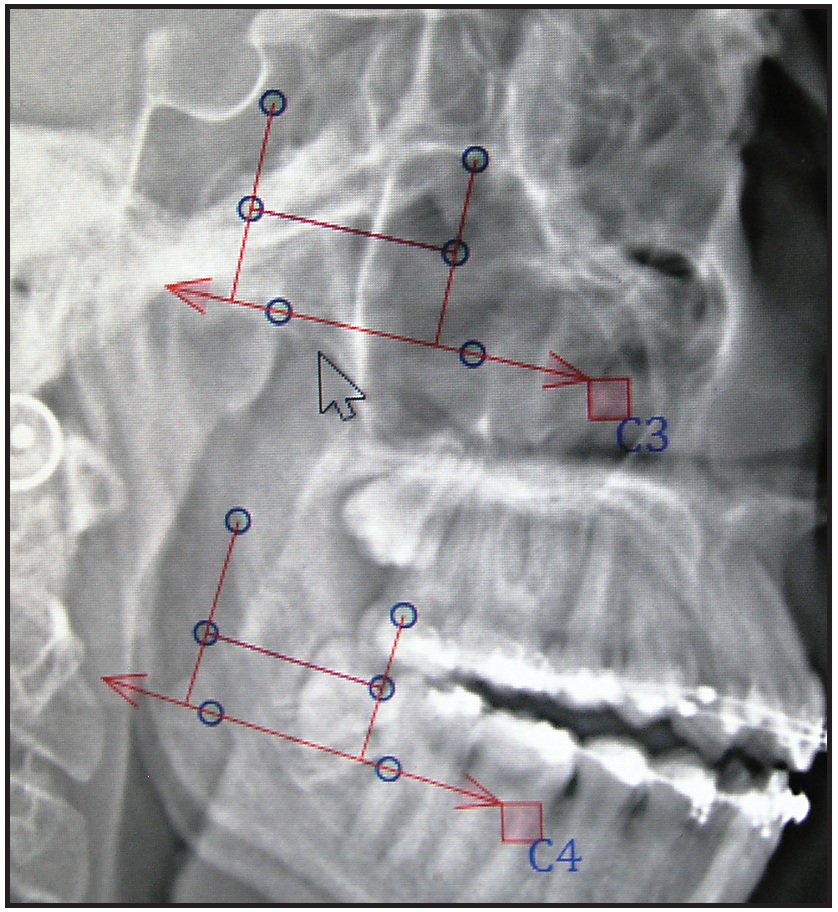

Fig. 4 Cervical vertebral landmarks included in software analysis. Blue reference plane appears after operator places superior and inferior points (points 1-4 in Fig. 5) with mouse.

Fig. 5 Blue circles moved by operator to indicate anatomical landmarks, with inferior and superior points placed first, followed by midpoints.

Fig. 6 Calculated skeletal age. (Blue midplane lines added by software are now covered by red horizontal midlines, after operator's placement of antero- and postero-midpoints.)